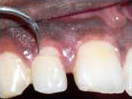

An Innovative Technique of saving a Tooth with Fracture Extending Sub-Gingivally (Chisel Type Fracture)

Tooth with Fracture Extending Sub-Gingivally

Showing picture line

Extending Palatally and

Sub-Gingivally.

X-ray showing

picture line

Labial Soft Tissue

Reflected

Palatal Soft Tissue